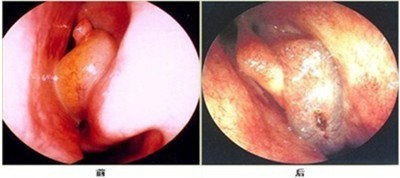

鼻窦炎的临床诊断和结果(以下图片可能引起不适,请谨慎浏览)

鼻内窥镜检查可见鼻粘膜慢性充血肿胀,鼻窦开口的区域可见有脓性分泌物,鼻窦透照,患病鼻窦透光不好。同时,检查可见患病鼻窦腔内密度均匀增高。

(图示:鼻窦炎前、后期的鼻内窥镜成像图)